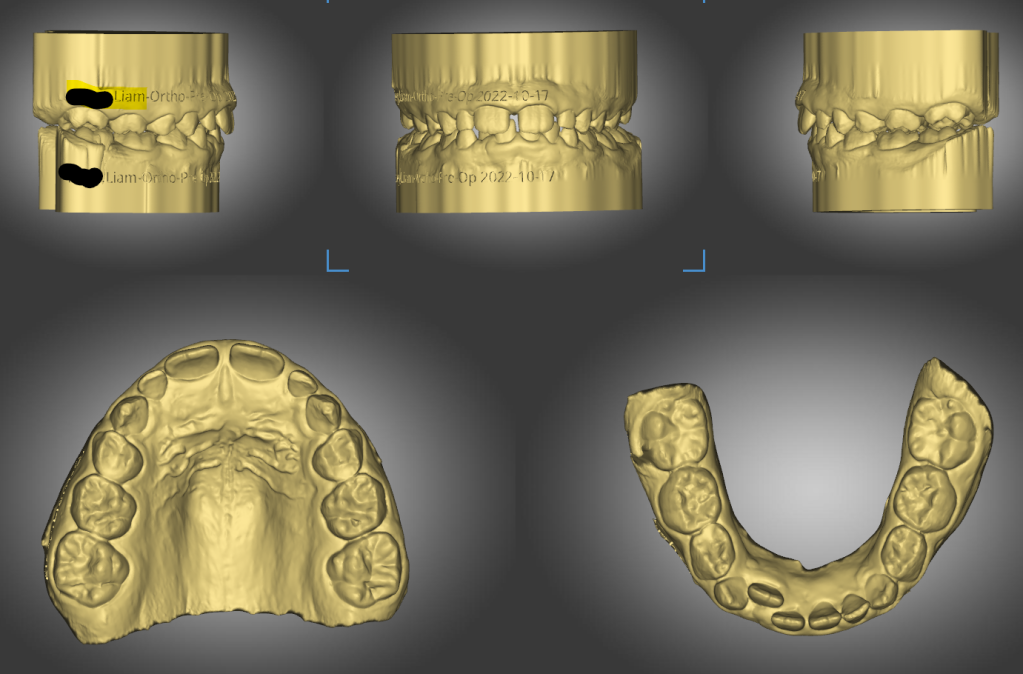

Pre-Op Records and Assessments

- Analysis

- Mixed dentition normal for age

- Class 1 molar with deep bite

- Upper central diastema – Tongue thrust may be a contributing factor

- Moderate to severe crowding as seen on OPG

- Unerupted 23 – tipped at nearly 45° mesially

- Unerupted 32 – rotated and entrapped. Deciduous 73 has not exfoliated because the 32 is not aligned with the root tip of the 72.